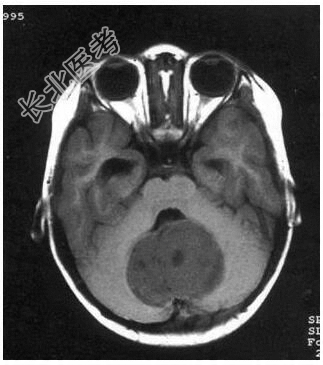

病历摘要:患儿男性,11岁。半年前开始出现行走不稳,常无故跌倒。半月前出现发作性剧烈头痛,伴恶心呕吐。体检:T36℃,P100次/分,R22次/分,BP100/60mmHg,神清,言语较缓慢,双眼外展约不及边,双眼侧视时有小幅度水平眼震。四肢肌力正常,右上肢肌张力较低,坐位姿势不稳,常不自主摇晃,双上肢指鼻不准,行走蹒跚步态,足距扩大,身前倾。患儿行头颅MR检查(见图)